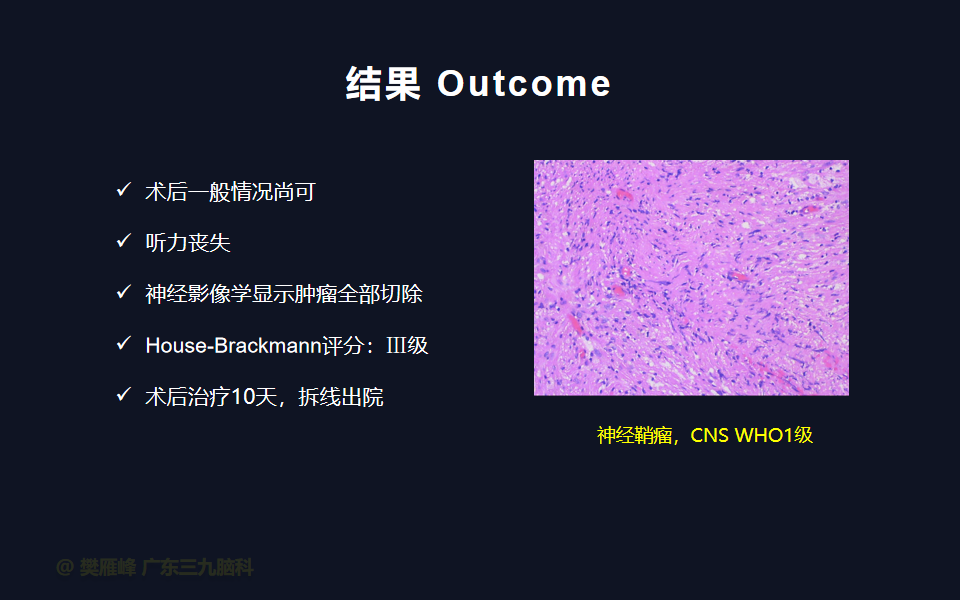

在这个二维手术视频中,展示了一种经枕下乙状窦后入路束膜下分离保留面神经的方法。患者是一名51岁的男性,有1年右耳听力下降伴耳鸣、无步态不平衡病史,术前有右侧轻度面瘫,神经影像学显示右侧桥小脑角区约30×30×29mm的囊实性占位,增强后实性部分及囊壁可见明显强化。他接受了经乙状窦后入路保留面神经的方法,术中肿瘤全切除,面神经被肿瘤挤压成薄膜状覆盖于三叉神经表面。术后面瘫加重,听力未能保留,神经影像学显示肿瘤全部切除。我们展示了安全的颅神经保护和肿瘤切除的细微差别和技术要点,以及手术技术。